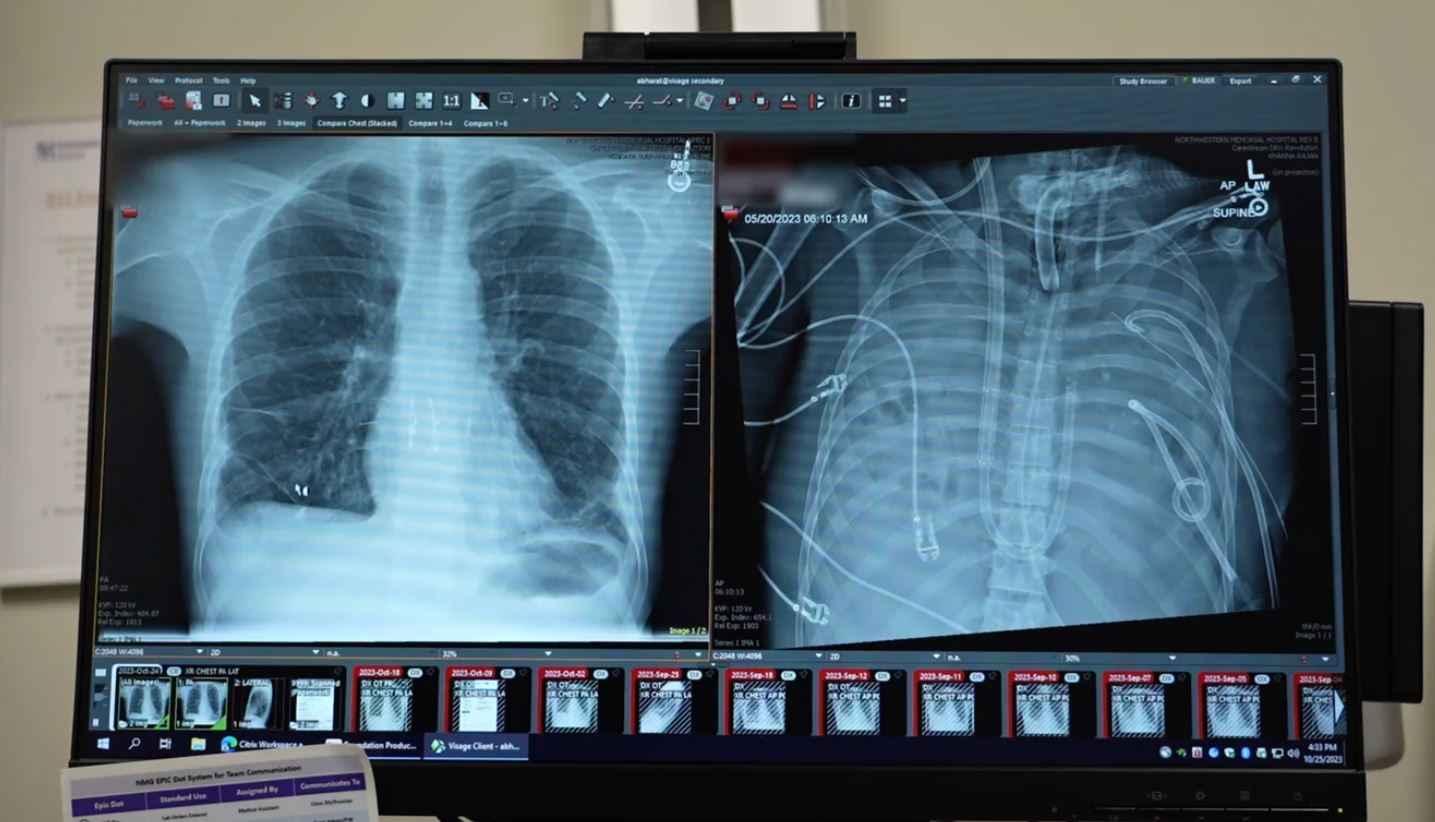

Hình ảnh bên trái cho thấy phổi mới (được cấy ghép vào bệnh nhân sau khi ông được duy trì sự sống bằng phổi nhân tạo) đặt cạnh phổi cũ của ông (bên phải). Ảnh: Northwestern Medicine